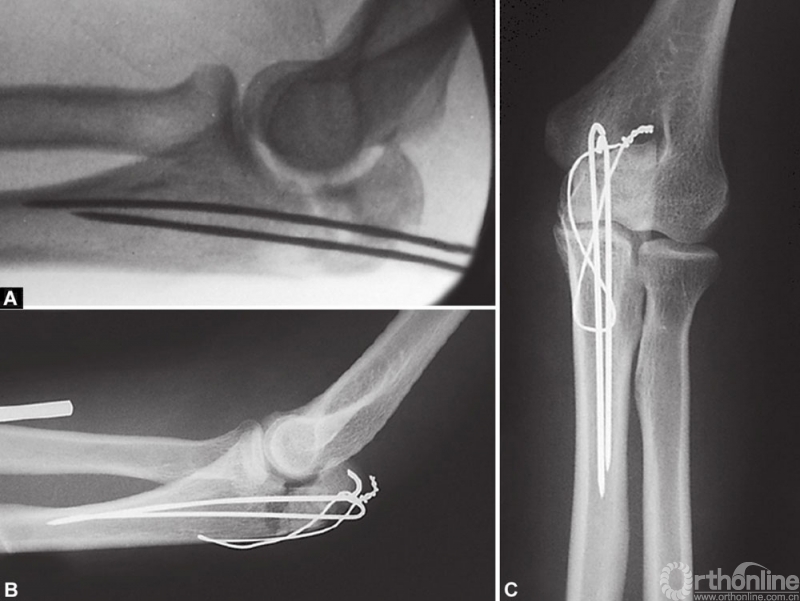

张力带钢丝将循环张力负荷转换为对骨折端的动态压缩力。这样,当患者活动肘关节时骨折端产生压应力,压应力促使骨折断端间产生的摩擦力能够维持复位直至骨折愈合。(图2A和B)显示了张力带钢丝固定简单横形鹰嘴骨折的良好作用,但不是斜形或粉碎骨折。

图2 A和B示意图展示了张力带钢丝治疗简单横形鹰嘴骨折的工作原理(A)对照斜形骨折(B);在图A中,伸肌和屈肌的拉力在骨折断面产生压缩力以维持复位,而图B中剪切力将导致骨折移位